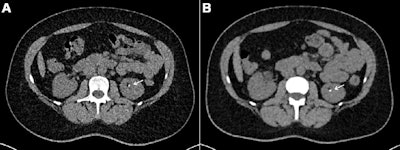

Axial contrast-unenhanced abdominal CT examinations in a 38-year-old female patient with a body mass index (calculated as weight in kilograms divided by height in meters squared) of 31.23 with known renal calculi for recurring events of flank pain. The patient underwent (A) dose-optimized energy-integrating detector CT (1.49 mSv) and (B) submillisievert photon-counting detector CT (0.94 mSv). Images from both examinations showed a 3-mm calculus in the left kidney (arrows). Images and caption courtesy of the RSNA.